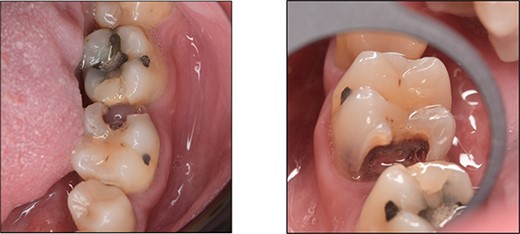

A 59-year-old male patient presented with a complaint of pain while biting on his lower left posterior teeth. Clinical examination revealed an extensive amalgam restoration on the lower left first molar (tooth 36) with a fractured restoration and secondary caries on the lingual aspect. The tooth was non-responsive to thermal testing and electrical pulp sensibility testing (EPT) and was tender to percussion. Radiographic examination showed radiolucency beneath the restoration on the mesial root surface, indicative of caries, along with furcation involvement and peri-radicular radiolucency. The tooth was diagnosed with pulpal necrosis and symptomatic apical periodontitis associated with extensive root caries (Fig. 6 and 7).

Clinical photograph of tooth 36 showing extensive amalgam restoration on mesio-occlusal-disto-bucco-lingual (MODBL).

Periapical radiograph of tooth 36 shows large radiopacity, indicating a restoration on the crown extending to the mesial root surface. Radiolucency was detected beneath restoration on the mesial root surface, indicating caries. Peri-radicular radiolucency was observed in the furcation region.